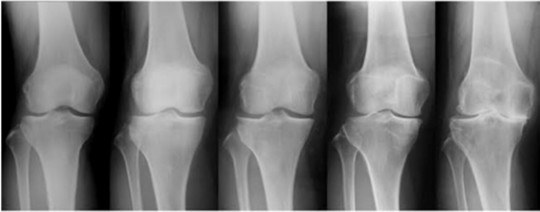

テニスで膝痛を発症させると、「半月板損傷」や「変形性膝関節症」を起こしている可能性があります。

膝が曲がらない、伸びない状態で、年齢が50歳以上であれば膝関節は、「変形」している可能性があります。

膝関節には、3つの動きがあります。

それは、『ころがり』『すべり』『回旋』の3つの動きになります。

膝が痛い方は特に、この『回旋』の動きがなくなる事が多くみられますが、そのほかにも『ころがり』『すべり』も制限されることは多くあります。

特に、膝の状態が悪くなればなるほど3つの関節の動きが制限されます。